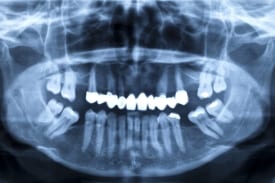

Unfortunately, not everyone is eligible for dental implants. This type of procedure comes with a few requirements that you must meet in order to receive treatment. First, you must have enough mass in your jawbone to support your dental implants. If you have lost several teeth many years ago, you may have missed your opportunity for standard dental implants. However, immediate dental implant treatment can help you retain bone mass. A proper candidate for dental implants will also have healthy gums and a full understanding of dental hygiene. If you abuse alcohol, use tobacco regularly, or suffer from certain chronic diseases, you may not be eligible for dental implant treatment. The only way to know for sure is to talk to your dentist.